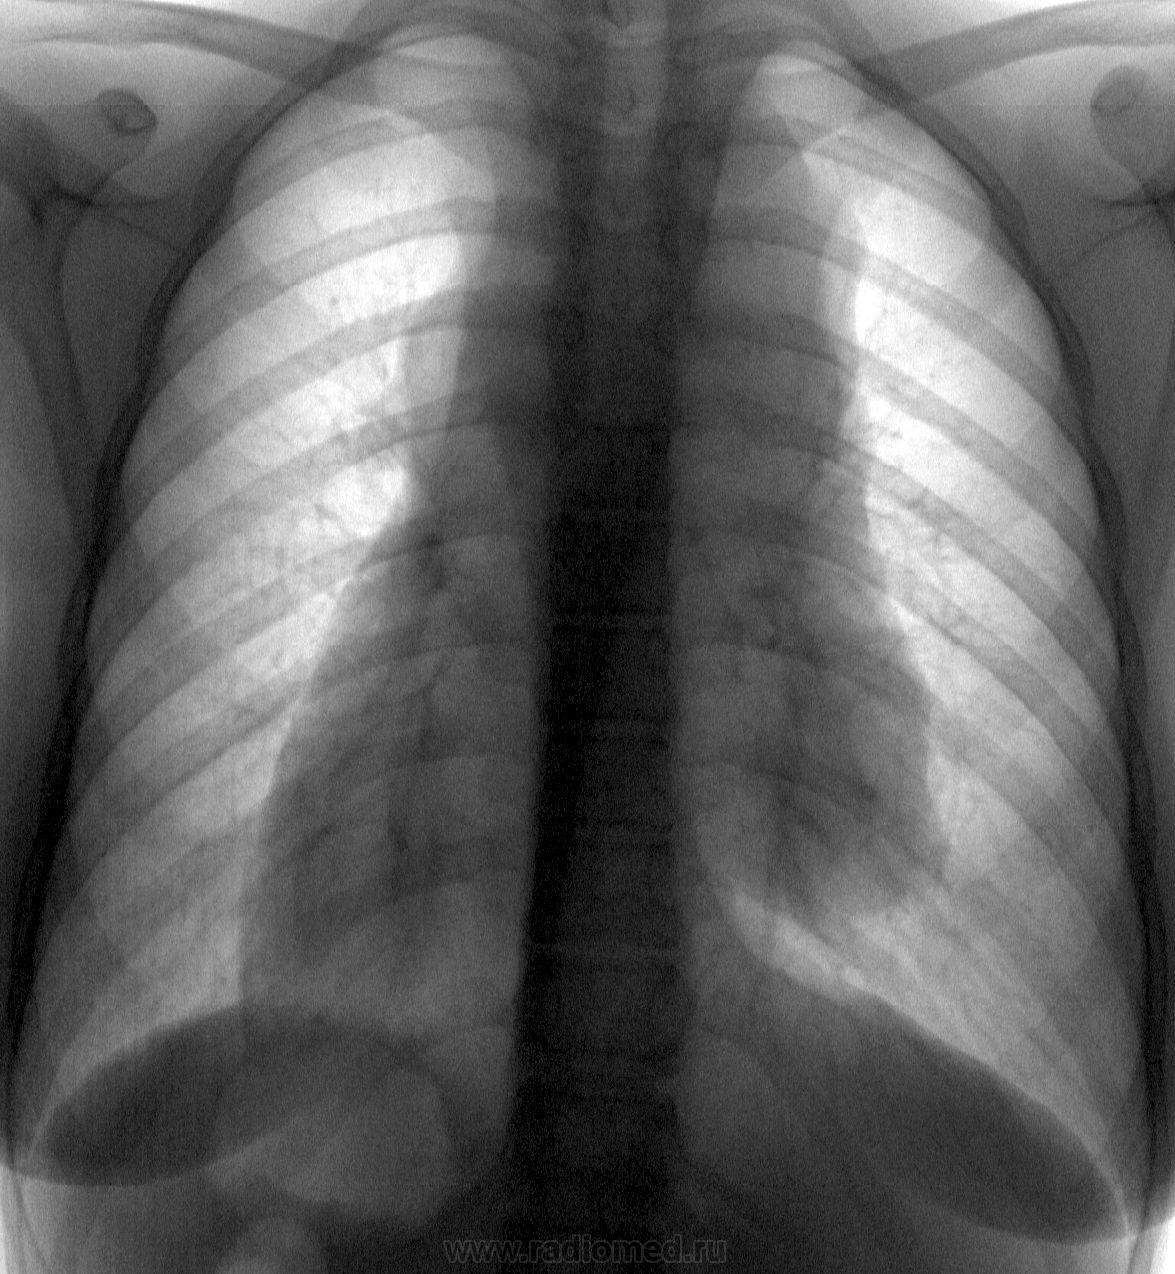

Нахожусь в подавленном настроении от вчерашнего случая. Несколько лет назад я подарил свой немецкий аккордеон, который не брал в руки более 30 лет после окончания муз. школы, практически незнакомой, подающей надежды девчушке, которая в силу обстоятельств (у родителей свои семьи) вынянчена и воспитывается бабушкой, санитаркой по професии. И вот сегодня она, победитель ряда местных конкурсов, выезжает на конкурс в Финляндию (визы, билеты и т.д. все с потугами бабушкой оплачено), а вчера она делала первую в своей жизни флюорографию. Отмечает тяжесть за грудиной. Низкий гемоглобин, высокое СОЭ (со слов бабушки).

Вроде про миастению  ни слова, но эдакий "хвостик" по нижнему контуру, более характерен для тимомы.

Пациентке надо провести КТ, возможно, с контрастным усилением. Имеется образование средостения, более выраженное справа, но его характер неясен. Я бы в первую очередь не предполагала бы тимому... Она едит поедзом или летит самолетом?

Какая-то лимфома. Лежала она и у нас в детской обл., и в столице в ОхМаДете. Волей-неволей, но это было у меня на слуху: то по FM радио услышу призыв на сбор средств на лечение, то по одному из каналов TV очень мной уважаемый певец, шоумен, соирался посетить ее в клинике и подарить аккордеон (не знаю, выполнил ли?), назвав ее очень талантливой девочкой...